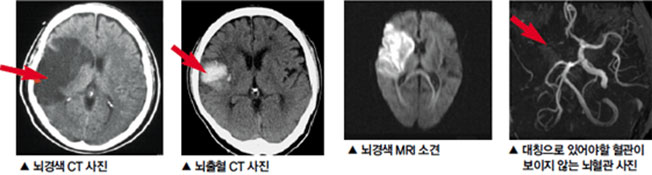

뇌경색이란 무엇인가요?

뇌경색은 뇌의 특정 부위에 혈액이 공급되지 않아 발생하는 문제입니다. 주로 혈관이 막히거나 좁아져 혈액이 제대로 흐르지 않을 때 발생하죠. 전 세계적으로 많은 사람들이 이 질환으로 고통받고 있으며, 특히 노인층에서 빈번하게 발생합니다. 뇌경색을 예방하고 조기에 발견하는 것이 중요한 이유는 이 질환이 뇌에 큰 손상을 줄 수 있기 때문입니다.